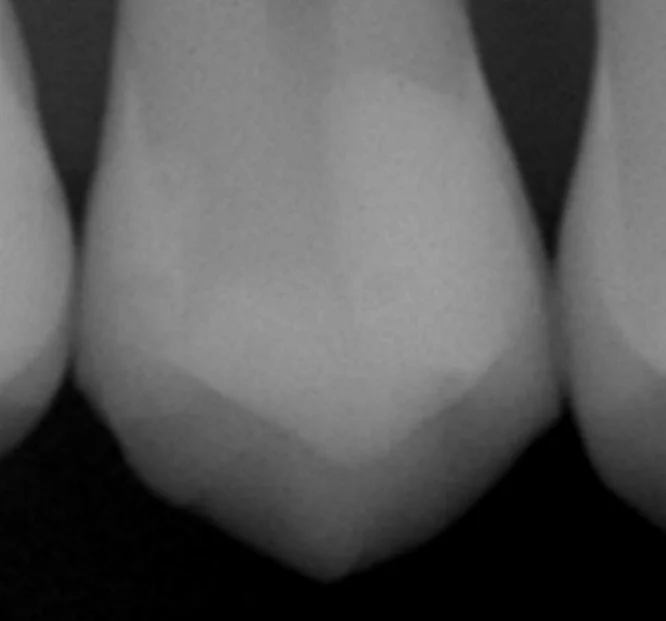

とはいえ、このサイズだと歯科医療従事者の場合実際の適合が安定しているのか気になると思いますので、合わせて経過のレントゲンも撮らせていただきましたので、それも載せておきます。

やや白みが強いところが詰めたレジンですね。

歯との間に一才の段差はなく、内部に虫歯が新たにできているような所見は全くありません。

歯としては、画面上の右側半分と左側の1/2がないような状態だったので1/4しか歯は残っていませんが、良好な状態をキープできています。